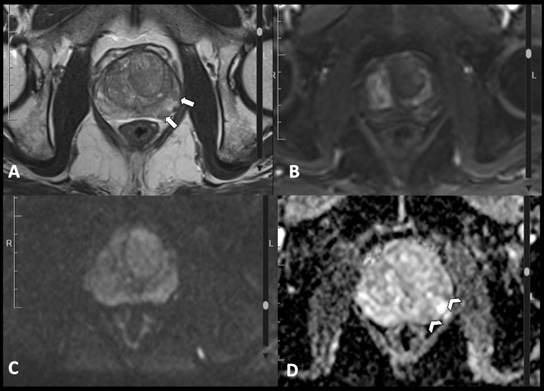

observador 3). Estos revisaron los estudios que cumplieron los criterios de inclusión (paciente con sospecha de carcinoma de próstata y RM con adecuados parámetros para su evaluación) mediante un visor de imágenes médicas (Hiruko, IMEXHS, Bogotá, Colombia). Calificaron las imágenes con los criterios principales del PI-RADS v. 2.1, consignaron los resultados en la herramienta de recolección descrita y emitieron una clasificación final para cada caso. En las Figs. 2, 3, 4, 5 y 6 se muestran ejemplos de las imágenes obtenidas y evaluadas según la clasificación PI-RADS v. 2.1.